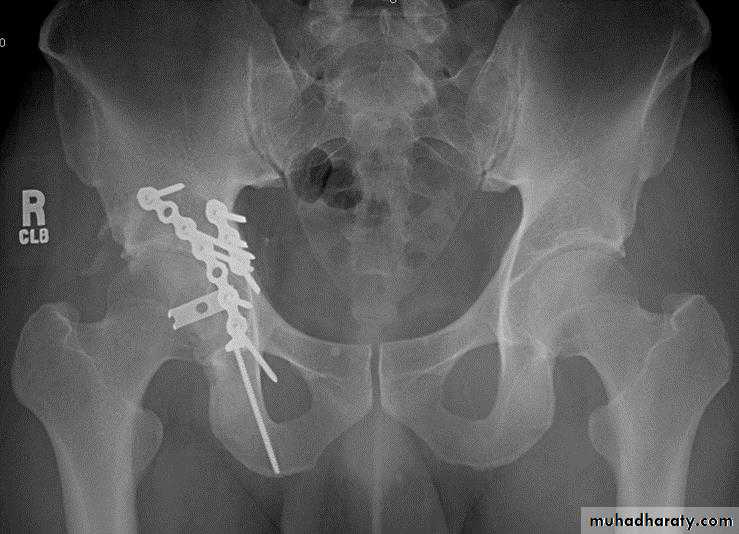

open reduction and internal fixationindications

physiologically stable

displacement of roof (> 2 mm)